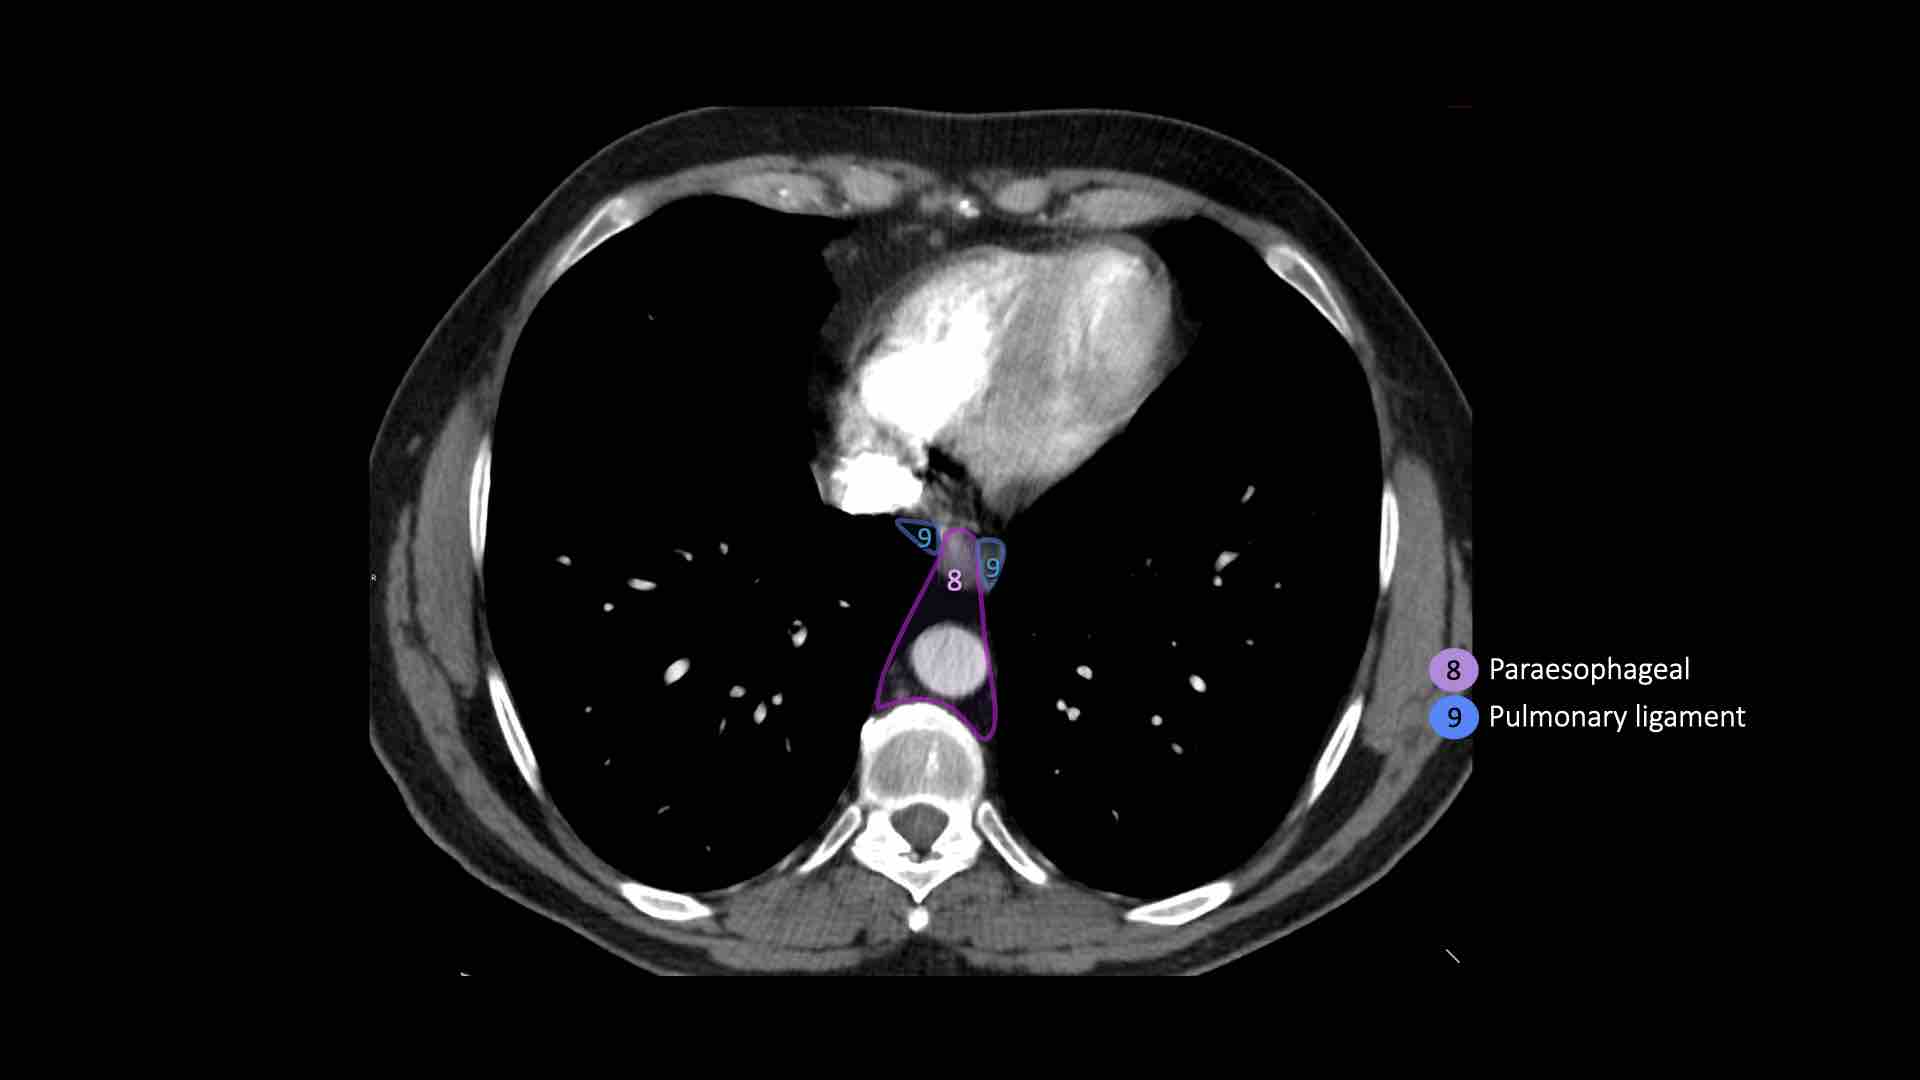

8. Cạnh thực quản

Các hạch nằm dưới carina.

9. Dây chằng phổi

Các hạch nằm trong dây chằng phổi.

8. Hạch cạnh thực quản

Các hạch này nằm bên dưới các hạch dưới carina và trải dài xuống đến cơ hoành.

Bên trái là hình ảnh dưới mức carina.

Bên phải thực quản là một hạch nhóm 8.

9. Hạch dây chằng phổi

Hạch dây chằng phổi nằm trong dây chằng phổi, bao gồm các hạch ở thành sau và phần dưới của tĩnh mạch phổi dưới.

Dây chằng phổi là phần kéo dài xuống dưới của các nếp gấp màng phổi trung thất bao quanh rốn phổi.

EUS-FNA

Siêu âm nội soi kết hợp chọc hút bằng kim nhỏ (EUS-FNA) có thể được thực hiện đối với tất cả các hạch bạch huyết trung thất có thể tiếp cận từ thực quản.

EUS đặc biệt hữu ích trong việc tiếp cận các hạch ở trung thất dưới (nhóm 7, 8 và 9).